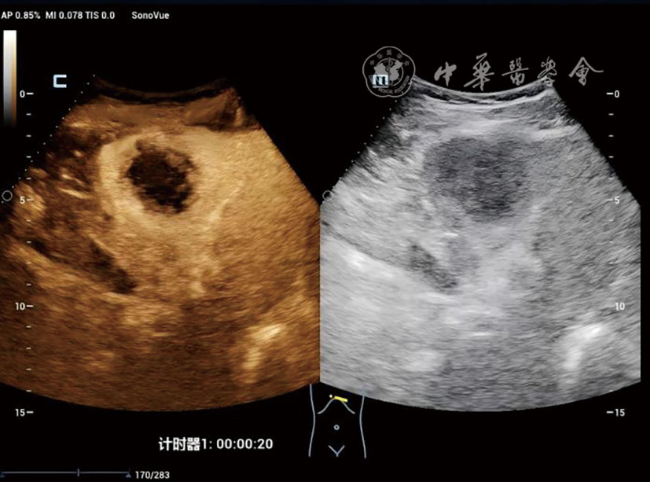

DPHCC组血清甲胎蛋白≥400 ng/ml的比例(48.4% vs 15.0%,P=0.002)及微血管浸润率(77.4% vs 17.5%,P<0.001)显著高于THCC组。超声造影显示,与THCC组相比,DPHCC组动脉期以不均匀增强(38.7% vs 15.0%)和环状增强(16.1% vs 2.5%)为主(P=0.003),且廓清时间更早[(91.94±37.58) s vs (131.65±59.71)s,P=0.002)]。多因素Logistic回归分析显示,肿瘤大小(OR=1.019,P=0.002)、甲胎蛋白≥400 ng/ml(OR=2.798,P=0.032)、边界不清(OR=3.204,P=0.020)及廓清时间<120 s(OR=2.221,P=0.049)是DPHCC的独立危险因素。

The DPHCC group showed significantly higher rates of serum alpha-fetoprotein (AFP) ≥400 ng/ml (48.4% vs 15.0%, P=0.002) and microvascular invasion (77.4% vs 17.5%, P<0.001) compared to THCC. On CEUS, DPHCC predominantly exhibited heterogeneous enhancement (38.7% vs 15.0%) and rim-like enhancement (16.1% vs 2.5%) in the arterial phase (P=0.003), with earlier contrast agent washout initiation (91.94±37.58 s vs 131.65±59.71 s, P=0.002). Multivariate analysis identified tumor size (odds ratio [OR]=1.019, P=0.002), AFP≥400 ng/ml (OR=2.798, P=0.032), ill-defined margin (OR=3.204, P=0.020), and washout time <120 s (OR=2.221, P=0.049) as independent risk factors for DPHCC.

表2 DPHCC组与THCC组患者的灰阶超声及超声造影特征比较[例(%)] |

廓清时间(s,![]() | 91.94±37.58 | 131.65±59.71 | t=3.41 | 0.002 |

| 动脉期增强方式 | - | 0.003 | ||

| 均匀增强 | 14(45.2) | 33(82.5) | ||

| 不均匀增强 | 12(38.7) | 6(15.0) | ||

| 环状增强 | 5(16.1) | 1(2.5) | ||

| 门脉期增强程度 | - | 0.060 | ||

| 高增强 | 1(3.2) | 4(10.0) | ||

| 等增强 | 4(12.9) | 13(32.5) | ||

| 低增强 | 26(83.9) | 23(57.5) | ||

| 实质期增强程度 | - | 0.157 | ||

| 高增强 | 1(3.2) | 0(0) | ||

| 等增强 | 0(0) | 3(7.5) | ||

| 低增强 | 30(96.8) | 37(92.5) | ||

| 内部灌注缺损 | χ2=0.13 | 0.722 | ||

| 无 | 27(87.1) | 36(90.0) | ||

| 有 | 4(12.9) | 4(10.0) |

注:DPHCC为双表型肝细胞癌;THCC为经典型肝细胞癌;-表示Fisher检验无统计值 |